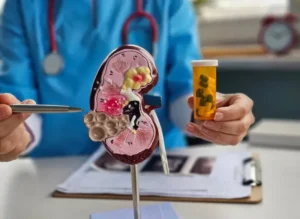

Kidney Stone

A hard, crystalline mineral formation that develops in the kidney and can cause severe pain.

Diagnosis & Treatment

Get accurate tests and a personalized treatment plan.